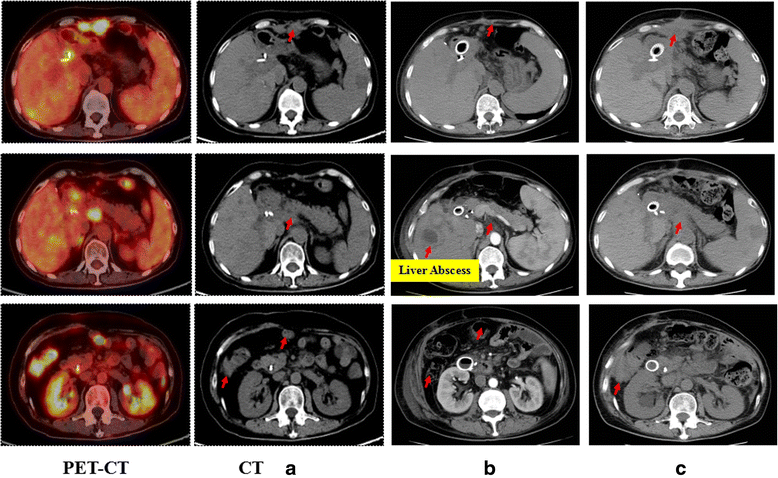

Case presentation: In this case, a 52-year-old female who was diagnosed as advanced unresectable/metastatic CCA and resistant to the following chemotherapy and radiotherapy was treated with CART cocktail immunotherapy, which was composed of successive infusions of CART cells targeting epidermal growth factor receptor (EGFR) and CD133, respectively. The patient finally achieved an 8. 5-month partial response (PR) from the CART-EGFR therapy and a 4. 5-month-lasting PR from the CART133 treatment. The CART-EGFR cells induced acute infusion-related toxicities such as mild chills, fever, fatigue, vomiting and muscle soreness, and a 9-day duration of delayed lower fever, accompanied by escalation of IL-6 and C reactive protein (CRP), acute increase of glutamic-pyruvic transaminase and glutamic-oxalacetic transaminase, and grade 2 lichen striatus-like skin pathological changes. The CART133 cells induced an intermittent upper abdominal dull pain, chills, fever, and rapidly deteriorative grade 3 systemic subcutaneous hemorrhages and congestive rashes together with serum cytokine release, which needed emergent medical intervention including intravenous methylprednisolone V体育安卓版. .